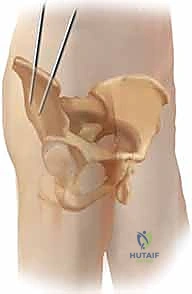

الخطوة الثانية: تحديد المعالم العظمية واستخدام الأشعة المرئية (C-Arm)

باستخدام جهاز الأشعة السينية المتحرك (Fluoroscopy) داخل غرفة العمليات، يقوم الدكتور هطيف بتحديد المعالم العظمية الدقيقة لضمان إدخال المسامير في الأماكن الأكثر كثافة وقوة في عظام الحوض (عادة فوق الحُق Supra-acetabular أو في العرف الحرقفي Iliac crest).

الخطوة الثالثة: إدخال المسامير المعدنية (Schanz Pins)

يتم عمل شقوق جلدية صغيرة جداً (حوالي 1-2 سم). من خلال هذه الشقوق، وبدقة متناهية لتجنب الأعصاب والأوعية الدموية، يتم إدخال مسامير معدنية سميكة ومصنوعة من التيتانيوم أو الفولاذ المقاوم للصدأ في عظام الحوض.